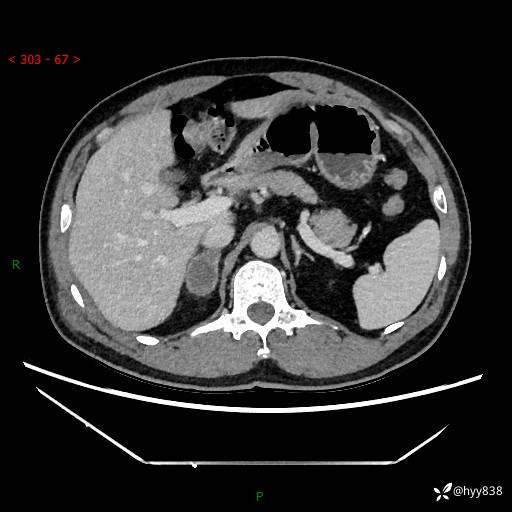

现病史:患者9月4日摔伤在深圳市宝安区中心医院行CT检查提示右侧肾上腺区结节(38*27mm),复查B超提示右侧肾上腺区可见一61*24mm异常低回声团,建议进一步检查。进一步完善增强CT后提示:右侧肾上腺区肿块及周围渗出改变,大致同前,考虑肾上腺腺瘤,不除外瘤内出血可能,否认阵发性头晕、头痛、出汗、乏力等不适,门诊以“ 右侧肾上腺肿瘤”收入住院。 起病来,患者精神、食欲、睡眠可,大便通畅,小便如上述,体力体重无明显改变。

肾上腺CT平扫

增强(动脉期+静脉期)